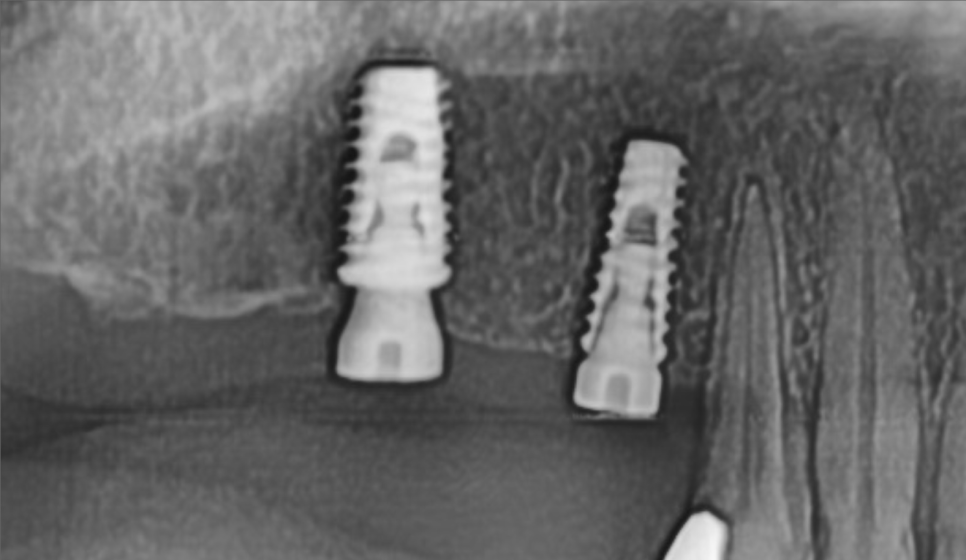

식립 이후의 파노라마 사진입니다.

수술 당시 골질은 D2정도로 상악임에도 단단하였고, 초기 고정은 각각 50N, 30N 이상, ISQ 또한 최대 80 가까이 나왔습니다.